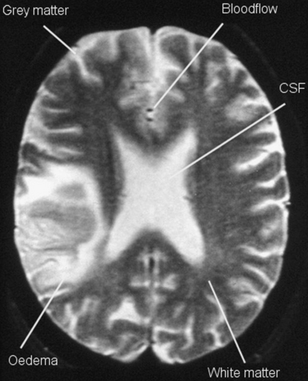

Now let’s look at Figure 39.7 (see page 292), a T2 weighted image. On a T2 weighted image, fluid appears bright. Fluid relaxes more slowly than fat in terms of the transverse recovery process. The bright signal from CSF in the lateral ventricles and oedema surrounding a brain tumour can be seen. Notice that fat and cortical bone appear grey or dark (the latter for the reason considered above) and are not well seen here. Grey matter, which contains many fluid-containing cell bodies, appears relatively bright, while the fatty myelinated axons of white matter appear grey. Once again flowing blood, seen here in two end-on blood vessels, does not give a signal as this is a spin echo image. T2 weighted images use a long TR and long TE and this contributes to making a T2 image relatively slow to acquire. It is more often affected by motion blur than a T1 image.

image

Figure 39.7 A T2 weighted axial spin echo image of the brain.